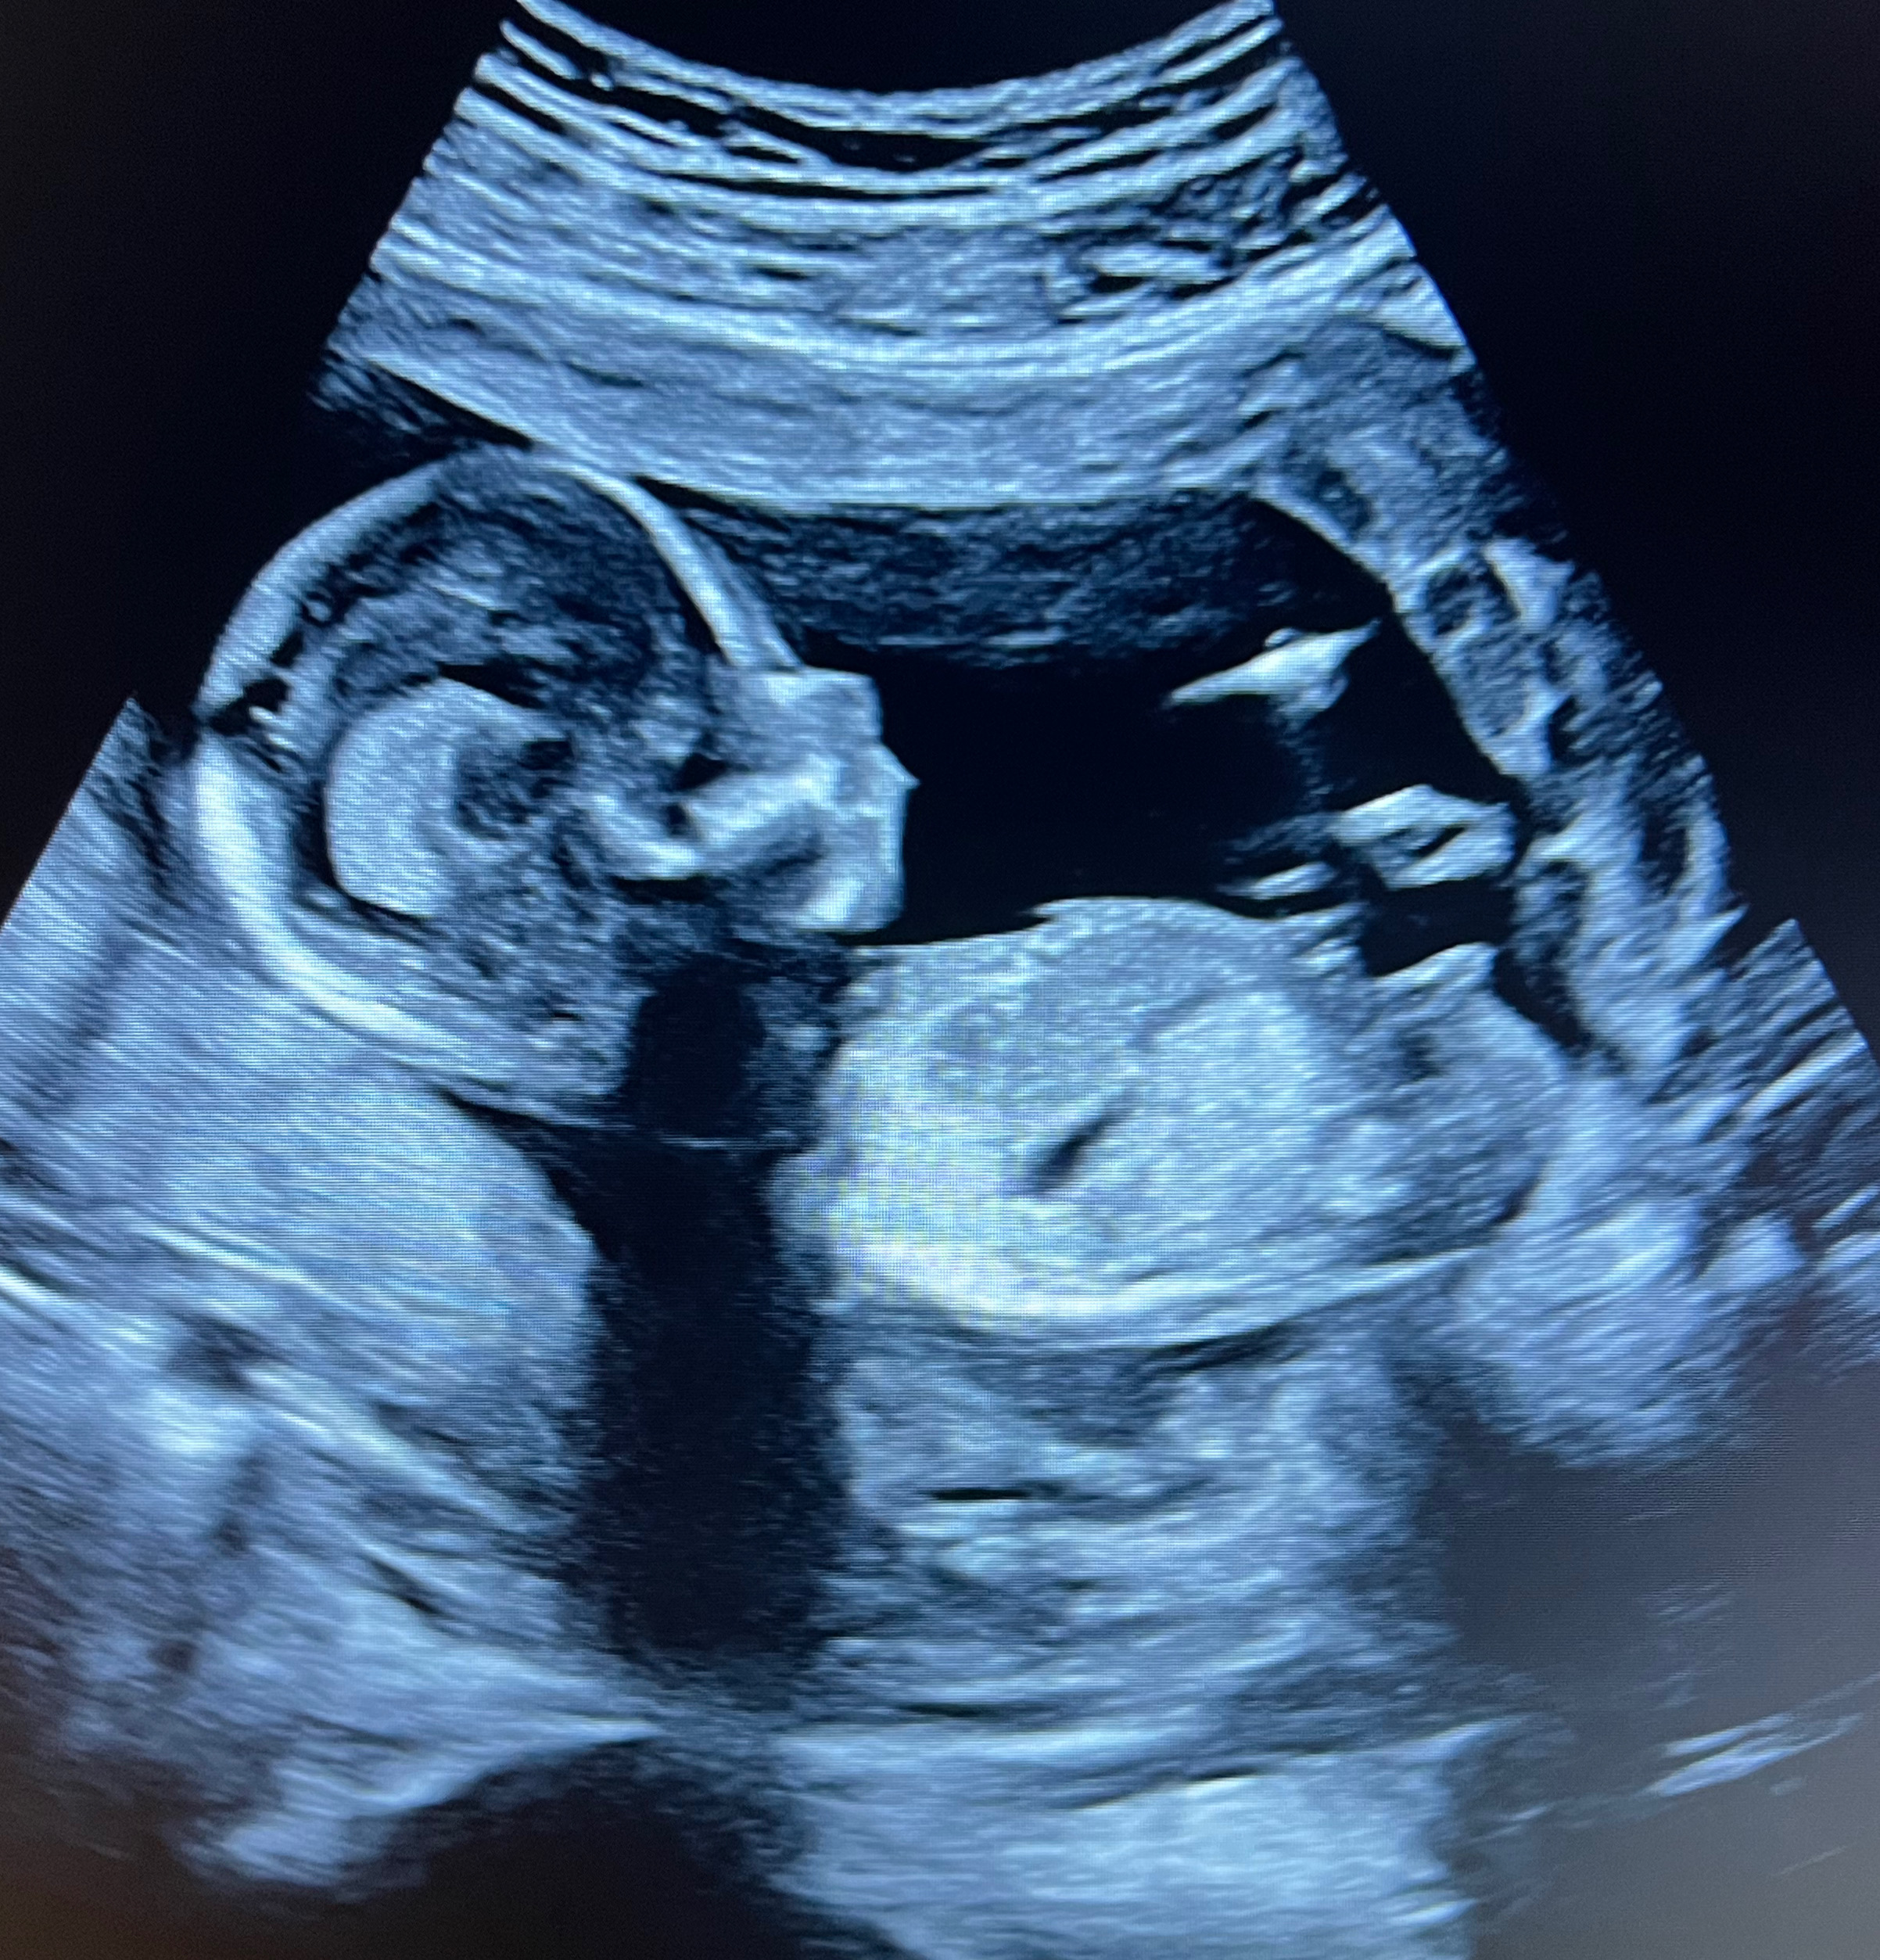

Een vroege echo kan worden ingepland vanaf 6 weken zwangerschapsduur. Veel eerder dan dat zou wel kunnen maar geeft je als zwangere niet meer informatie. De hartactie van de baby begint te kloppen bij 5 weken en 4 dagen, maar is heel vaak met de echo pas zichtbaar na 6 weken zwangerschap. Om onzekerheid te voorkomen of de zwangerschap wel of niet goed is zien wij je dus het liefst pas na 6 weken zwangerschapsduur.

Vroege echo

Vanaf 6 weken tot 10 weken 10 min, inclusief 2 zwart/wit foto afdrukken (dit is altijd een echo via de buik) . Dit is de eerte echo na een positieve test en kan al voordat je bij de verloskundige terecht kan gemaakt worden bij ons. We kunnen metingen doen wat betreft het aantal weken en bekijken of er een kloppend hartje te zien is! Je weet dus direct hoe ver je bent en of alles goed zit!